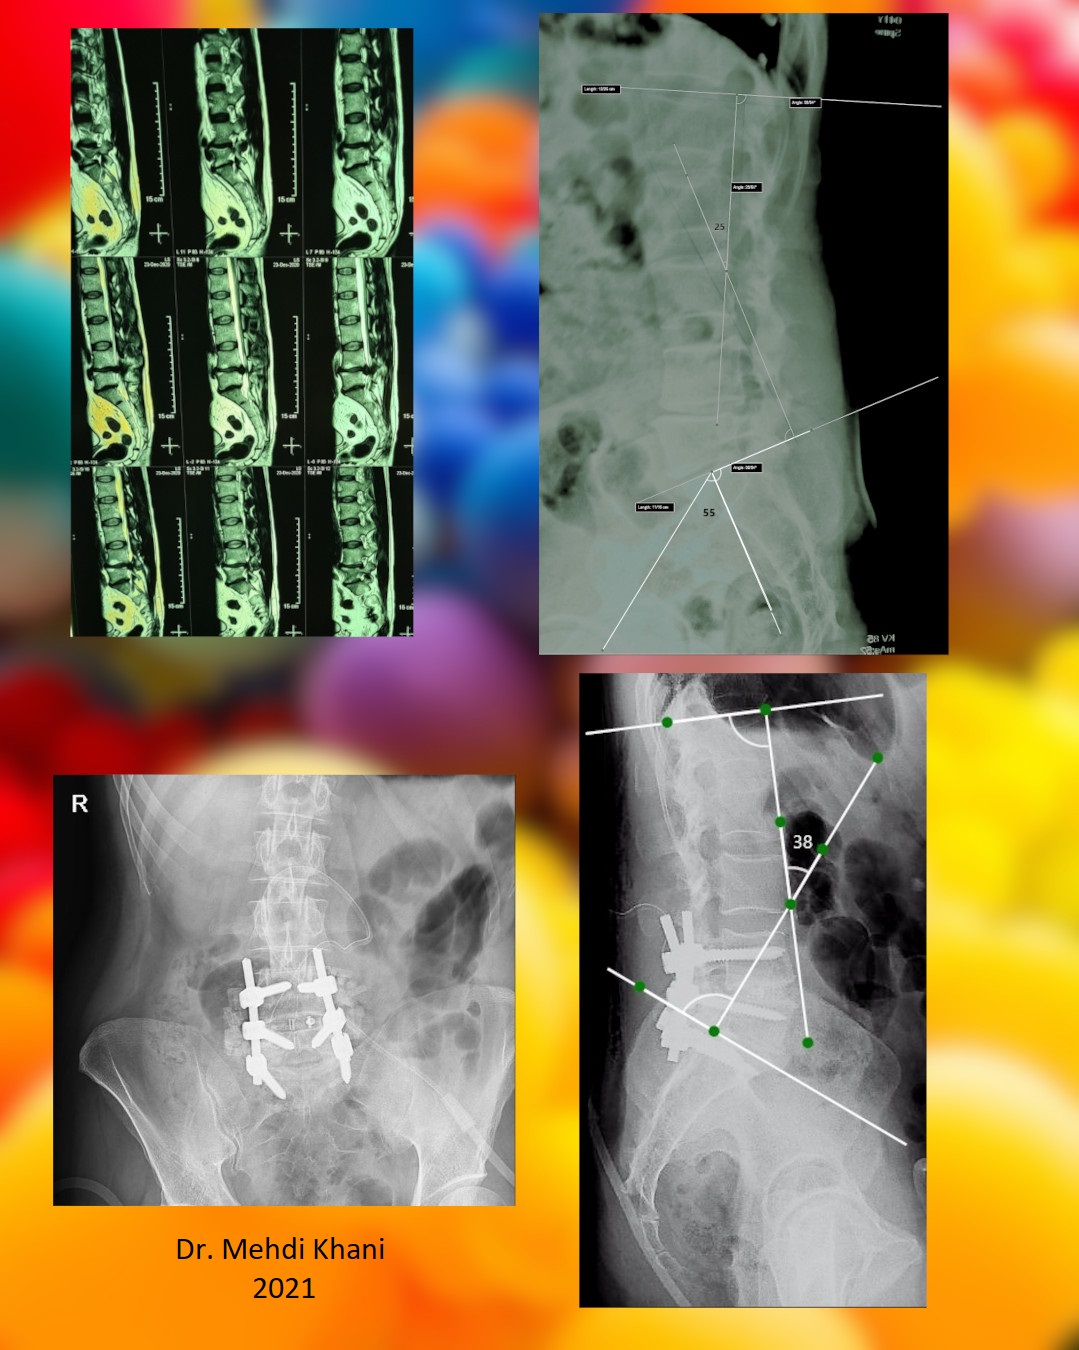

آقای ۴۵ ساله با درد شدید کمر و پای راست مراجعه کرده بودند. عکسهای بالا عکسهای قبل از عمل ایشان را نشان می دهد. همانطور که می بینید کمر قوس طبیعی ندارد و صاف می باشد (قوس کمر ۲۵ درجه و PI پنجاه و پنج درجه می باشد). عکسهای پایین عکسهای پس از عمل می باشند که با کمی کوتاه کردن پشت مهره که Ponte osteotomy نام دارد و گذاشتن کیج بین مهرهای ۴ و ۵ زاویه اصلاح شده (قوس کمر ۳۸ درجه). بیمار روز پس از عمل احساس راحتی در ایستادن و راه رفتن پیدا کرد.